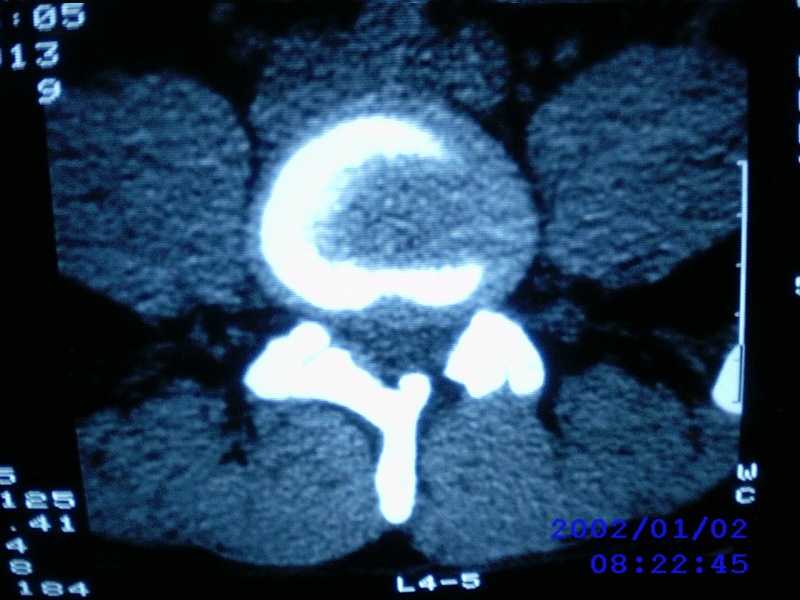

患者,男性,40岁,腰痛伴左下肢疼痛、麻木6年。5年前做过腰椎间盘手术,具体是哪个位置病人记不清了。

我拍的是l4-5、l5-s1

1)l4/5及l5/s1左侧椎板术后改变。2)l5/s1椎间盘突出,l5椎体下缘许莫氏结节。3)l4/5椎间盘膨出并突出。4)l3/4椎间盘膨出。

1)l4/5及l5/s1左侧椎板术后改变。2)l5/s1椎间盘突出,l5椎体下缘许莫氏结节。3)l4/5椎间盘膨出并突出。

1)l4/5及l5/s1左侧椎板术后改变。2)l5/s1椎间盘突出,l5椎体下缘许莫氏结节。3)l4/5椎间盘膨出并突出。4)l3/4椎间盘膨出。支持!